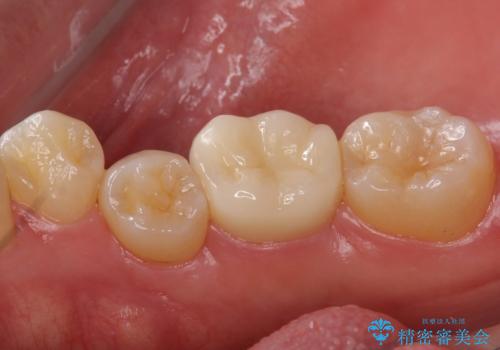

奥歯の詰め物の変色 セラミッククラウンでのやり替え

同じ樹脂の材料で詰め直しをしたところでまた変色してしまうリスクが高いため、セラミックでの治療となりました。

- 左下6 仮歯+セラミッククラウン 11000円+110000円費用は治療当時の料金となります

樹脂の材料はどうしても変色などの劣化スピードが速いです。

樹脂の変色が気になる場合は、劣化しにくいセラミックに材料ごと変えることをお勧めします。